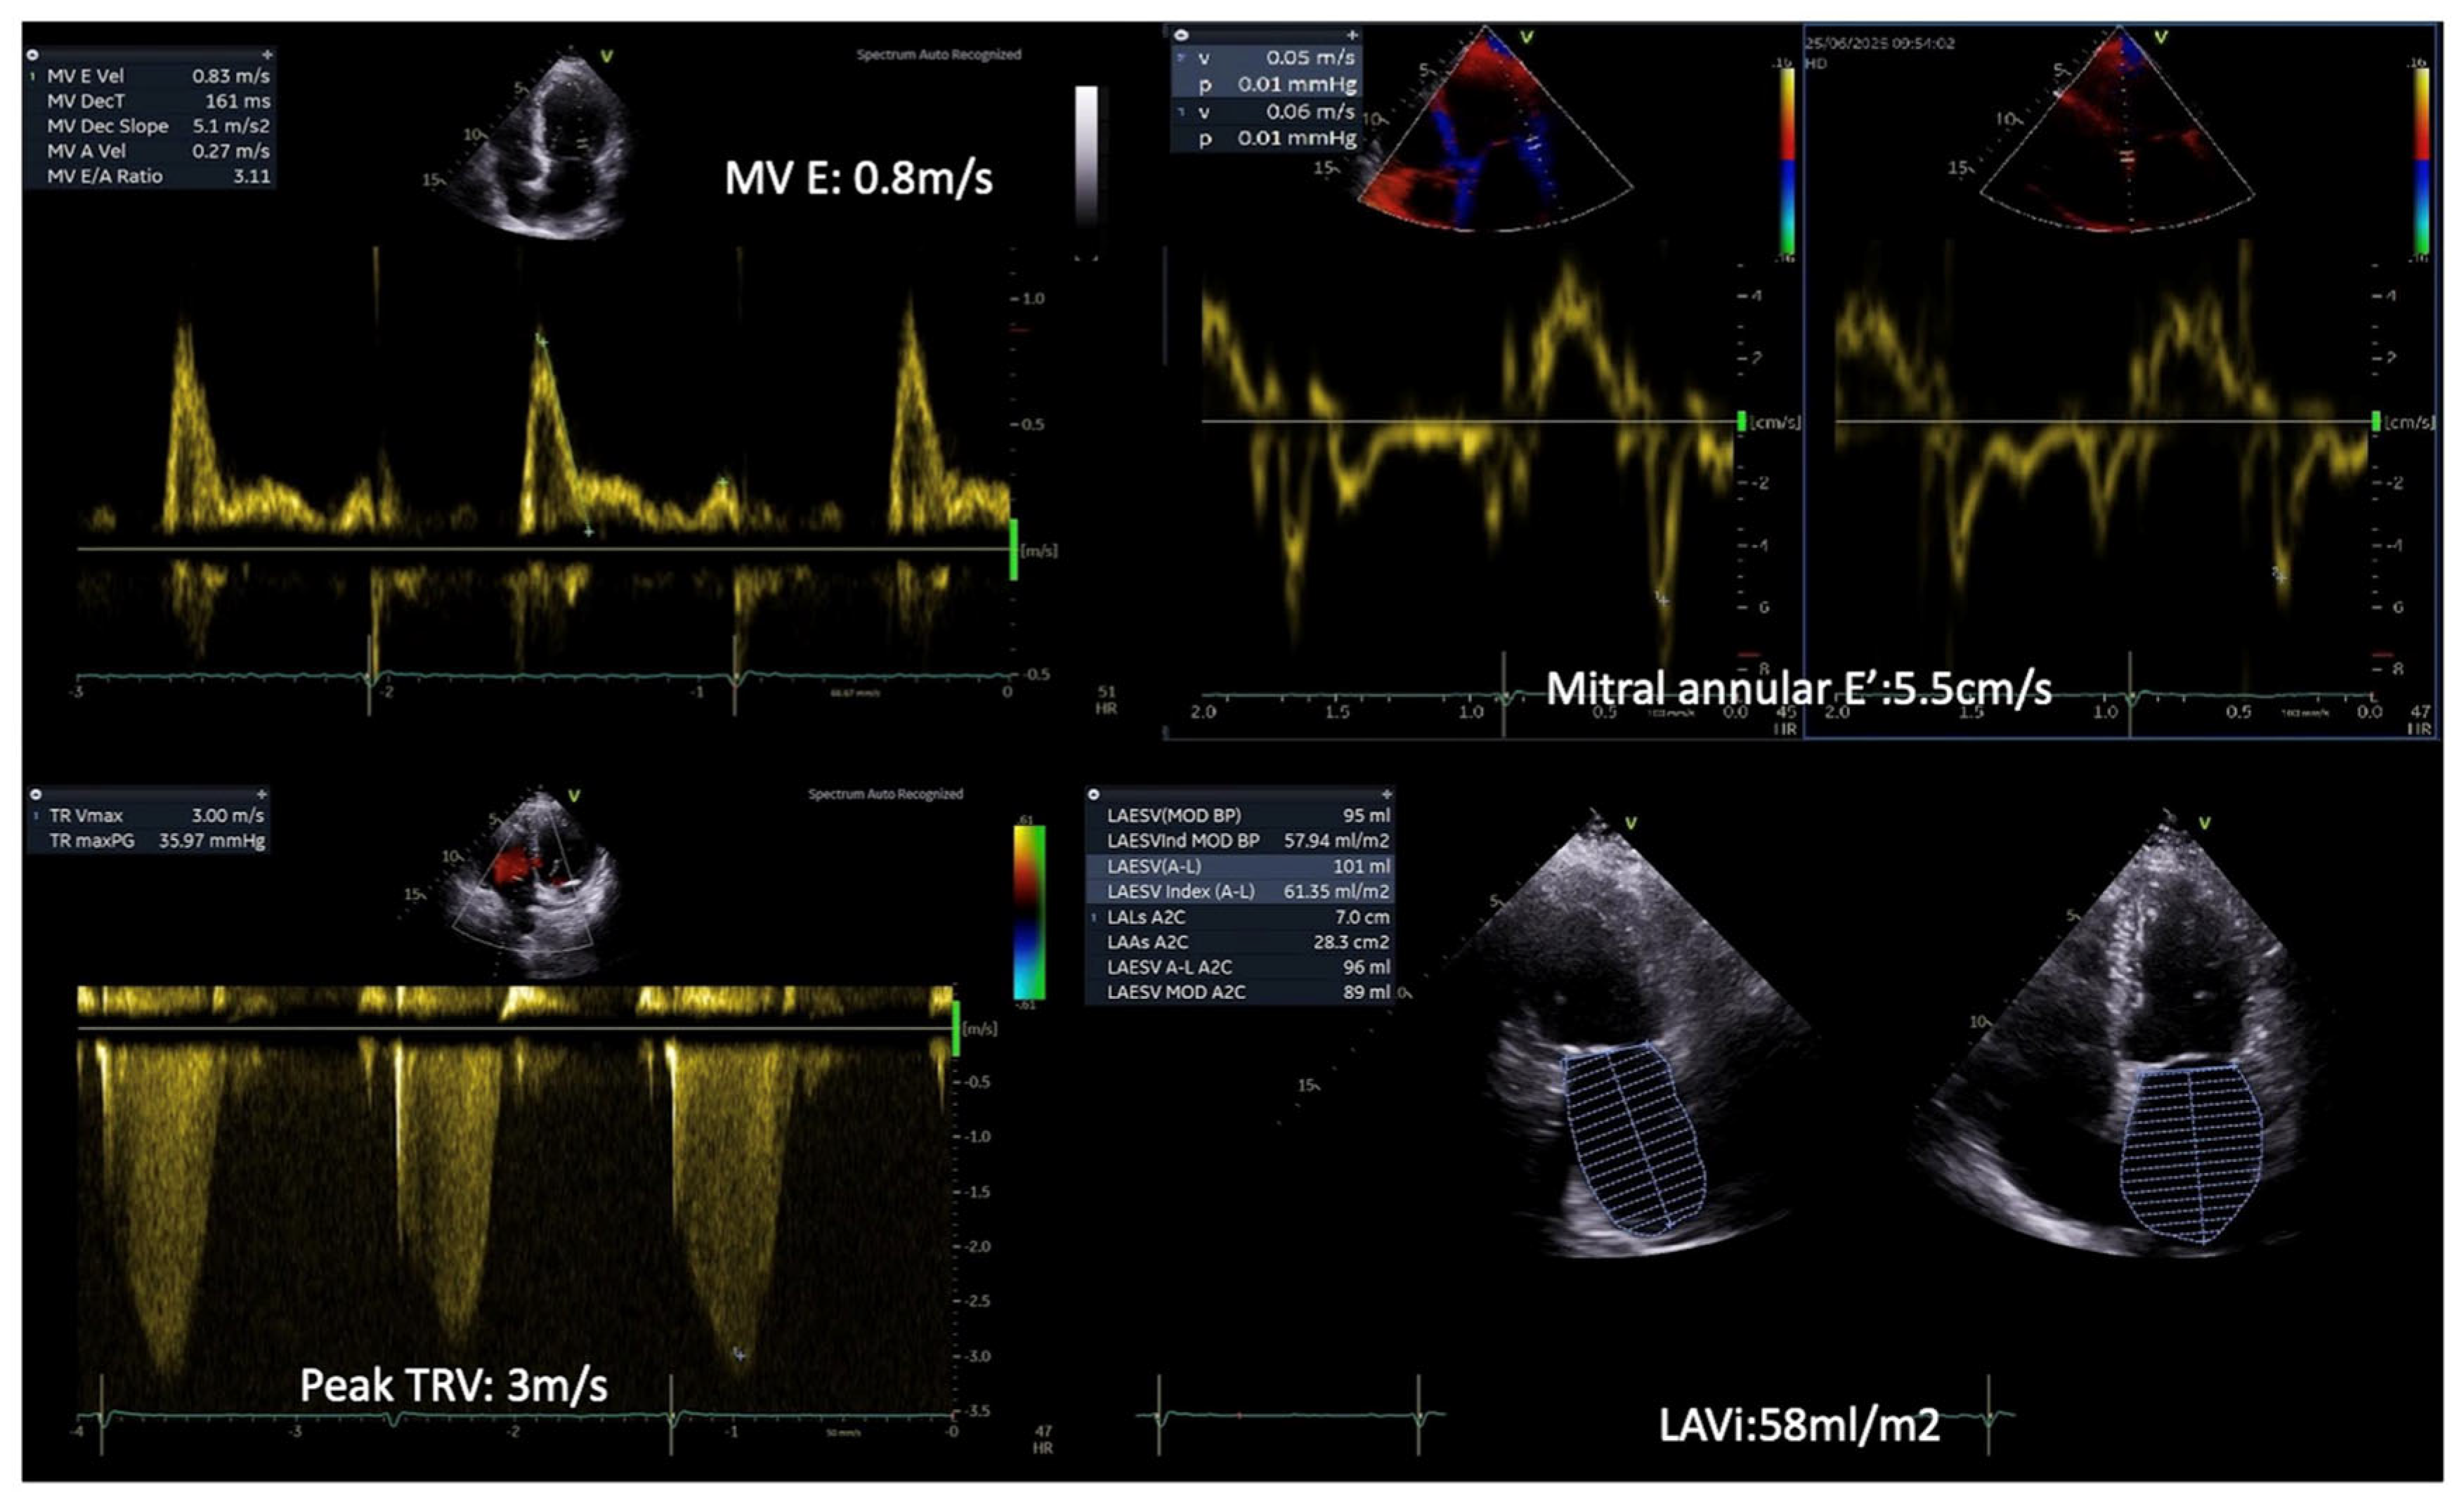

4.1. Speckle Tracking Echocardiography of the LV

STE has emerged as a valuable imaging modality in detecting subclinical myocardial dysfunction in DBCM [68]. Traditional echocardiographic parameters, such as LVEF, often remain within normal limits in the early stages of DBCM, limiting their utility in identifying subtle myocardial abnormalities [69]. In contrast, STE enables the quantification of myocardial deformation by assessing global and segmental strain patterns, thereby offering superior sensitivity in detecting early systolic and diastolic dysfunction [69,70] (Figure 3). Among the various strain parameters, GLS has been extensively validated as a robust marker of myocardial dysfunction. Several studies have demonstrated that diabetic patients exhibit significantly reduced absolute GLS values compared to non-diabetic controls, even when LVEF is preserved [6,71]. A GLS value above −18% is considered indicative of early myocardial impairment, correlating with both metabolic dysregulation and cardiovascular risk [72]. Furthermore, longitudinal strain impairment has been shown to precede changes in circumferential or radial strain, highlighting the vulnerability of longitudinal subendocardial fibers to diabetic metabolic disturbances, fibrosis, and microvascular dysfunction [72,73].

Importantly, GLS also holds significant prognostic value in patients with DBCM. Reduced absolute values of GLS have been independently associated with adverse cardiovascular outcomes, including HF hospitalization, major adverse cardiac events (MACE), and all-cause mortality, even in diabetic individuals with preserved LVEF [74,75]. A longitudinal study by Ersbøll et al. demonstrated that impaired GLS was a stronger predictor of cardiovascular mortality than LVEF in patients with diabetes and established heart disease [76]. Moreover, in asymptomatic individuals with type 2 diabetes mellitus and normal LVEF, subclinical LV dysfunction identified by impaired GLS was shown to be an independent predictor of all-cause mortality and hospitalization over nearly a decade of follow-up [77]. Complementing these findings, reduced absolute GLS has also been linked to myocardial microvascular dysfunction even in the absence of overt fibrosis, suggesting that impaired strain reflects early, preclinical myocardial injury in diabetic populations [78]. The above notions support the incorporation of GLS into routine echocardiographic evaluation for risk stratification in DBCM, facilitating earlier identification of high-risk patients who may benefit from closer surveillance or early therapeutic intervention. As such, GLS offers not only diagnostic but also prognostic utility, reinforcing its central role in the evolving echocardiographic assessment of diabetic myocardial involvement.

Beyond GLS, global circumferential strain (GCS) and global radial strain (GRS) provide complementary insights into myocardial deformation. While GLS typically declines first, GCS and GRS impairments become more evident as the disease progresses [75]. Additionally, segmental strain analysis using STE has revealed that the basal and mid-segments of the left ventricle are more affected in DBCM, which may play a role in diastolic dysfunction and increased myocardial stiffness [79].